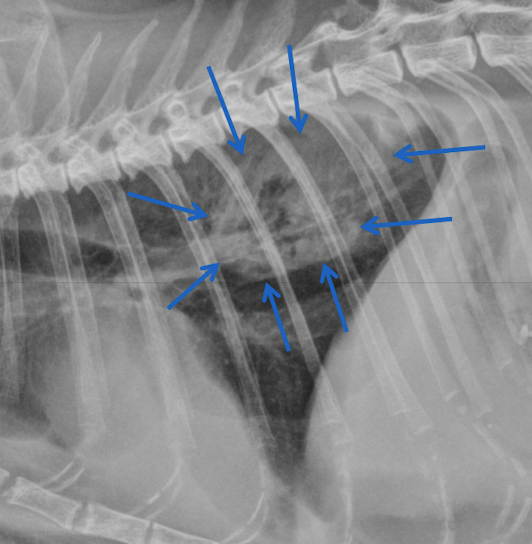

what kind of pattern

A

normal- left

interstitial- right